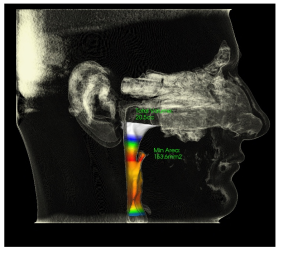

Airway:

• Airway MCA: 153.6mm2 (at risk for OSA less than 150mm2)